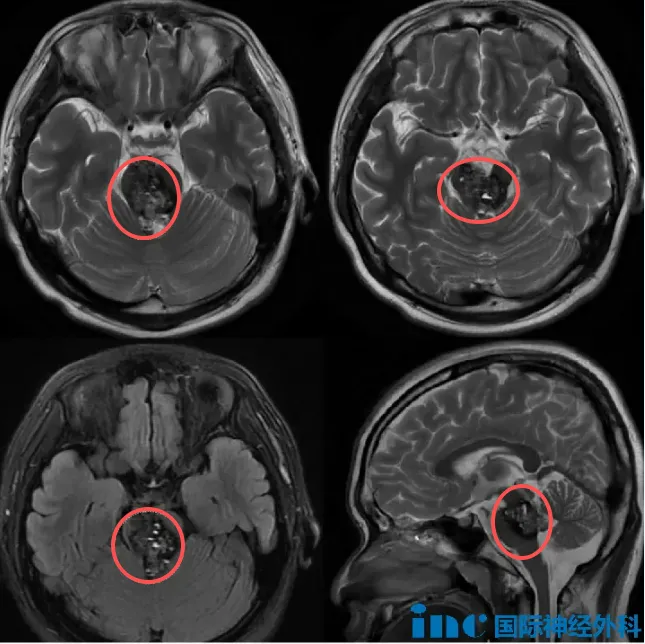

神经外科手术室内,一台高难度开颅手术正在进行中。患者为16岁男性少年,巴教授正在逐步切除其脑干内弥漫性分布的海绵状血管瘤。

16岁少年被诊断为巨大脑干海绵状血管瘤。复杂病情使众多医生感到棘手,病灶不仅体积巨大,内部还伴发出血。即使巴教授查看MRI后也说明:"其他多发海绵状血管瘤患者,病灶通常分散存在,脑干内可能仅有1-2个病灶,但该患者所有病灶均集中于脑干区域。"

脑干作为生命中枢,在此区域切除肿瘤本已极为困难,更何况是弥漫性分布的大小病灶。此外,该海绵状血管团占据中脑区域,甚至从前向后将桥脑"截断",处理难度极高。